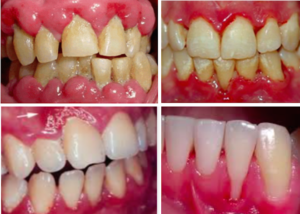

Quais os primeiros sinais da periodontite de início precoce?

Fique atenta a gengivas que sangram facilmente durante a escovação ou ao usar fio dental, vermelhidão e inchaço nas gengivas, mau hálito persistente, e em casos mais avançados, retração gengival e mobilidade dos dentes.